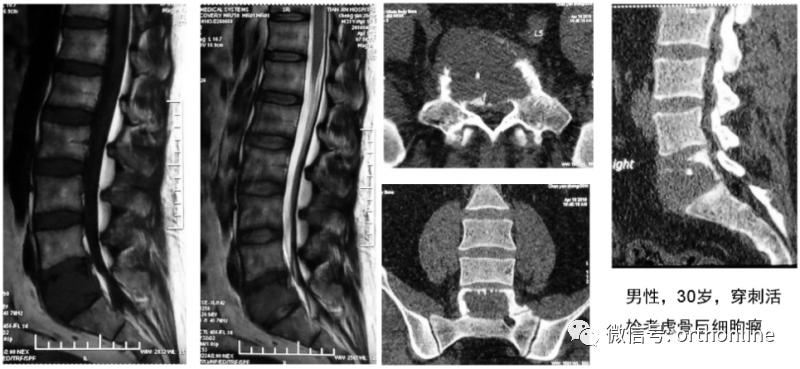

此前,有一例腰5椎体肿瘤患者在前路切除后进行椎体重建,以往临床上都是在术中给患者翻身进行后路固定。马信龙教授团队在做术前设计时,就给这名患者设计了个性化人工椎体,预留了假体与骨结合部位从前向后打椎弓根钉的孔,不需要患者翻身进行后路固定就获得了稳定性,临床效果令人满意。此例前路腰骶部病变切除后采用自主设计的3D打印假体重建椎体稳定性的病例,尚属国际首例。

这例前路腰骶部病变切除后,采用该院自主设计的3D打印假体重建稳定性的病例,尚属国际首例。

一例前路腰骶部病变患者术前影像片